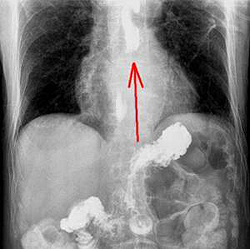

Вирусный эзофагит.

При компьютерной томографии определяется утолщение стенки пищевода более 5 мм со значительным утолщением складок слизистой оболочки (стрелки)

- Без контрастного усиления: утолщение стенки пищевода более 5 мм.

- С контрастным усилением: утолщение стенки пищевода более 5 мм и симптом «мишени» (отек подслизистой оболочки и интенсивное накопление контрастного препарата измененной слизистой оболочкой).